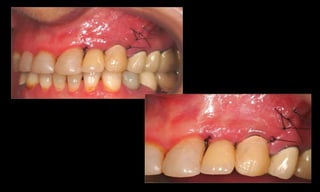

10-10-2005

Novembro de 2005

24-01-2006

Cone Morse